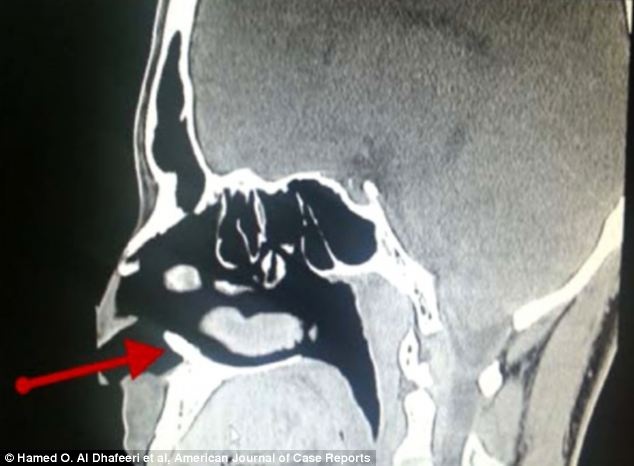

Các bác sĩ phẫu thuật và lấy chiếc răng dài 1 cm mọc bất thường trong mũi một người đàn ông Ả Rập.